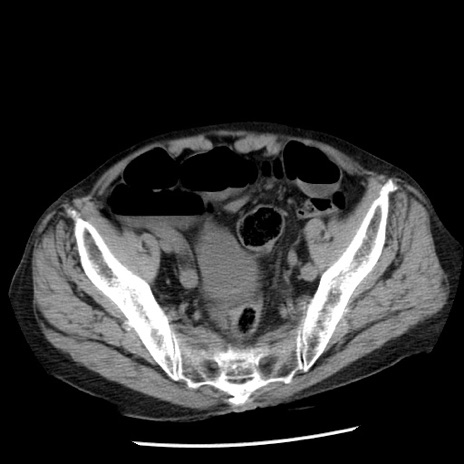

症例26(横断像)

【症例】80歳代男性

【主訴】嘔吐

【現病歴】昨晩2回嘔吐あり、今朝になっても嘔吐あり。来院。

【既往歴】胃潰瘍

【身体所見】意識清明、BT 37.6℃、BP 166/95mmHg、HR 100bpm、SpO2 97%、腹部:平坦・軟、腸蠕動音聴取良好、圧痛なし。

【データ】WBC 21900、CRP 1.46